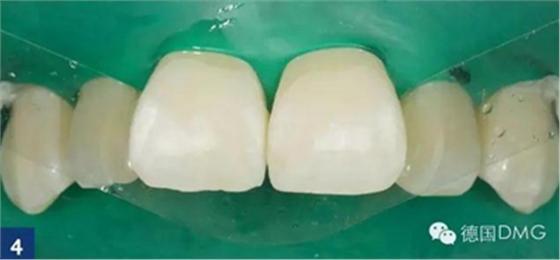

由于最初的酸蝕結(jié)果并不令人滿意,因此我們重復(fù)酸蝕步驟. 利用乙醇干燥之后,可以看到顏色的改變。但是酸蝕結(jié)果還是不滿意,因此我們進(jìn)行了第三次酸蝕。在每一次酸蝕之后, 都應(yīng)將酸蝕劑徹底沖洗干凈然后用icon干燥劑進(jìn)行干燥 (Fig. 4).